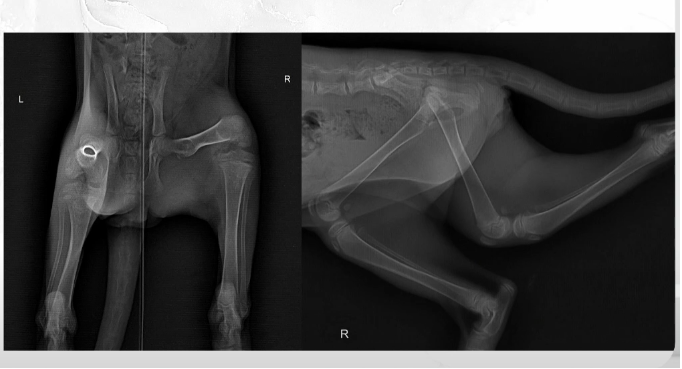

Но ветврачи регулярно сталкиваются с последствиями такой логики. На рентгеновских снимках у животных фактически не видно костей.

Вот так выглядят кости котенка, который не получает кальций: на снимке они почти прозрачные. Фото из презентации Дарьи Маслаковой.

Такая картина типична для вторичного алиментарного гиперпаратиреоза. Если объяснить проще: из костей питомца вымывается кальций, они становятся хрупкими и почти невидимыми на рентгене. Причина – в неправильном питании.